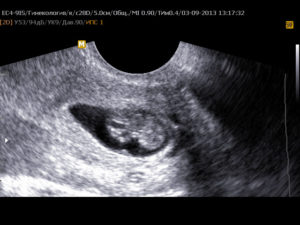

К концу 7-й недели зародыш уже приобретает свою характерную форму в виде буквы С. В это время он уже открепился от поверхности плодного яйца. На УЗИ уже можно различить голову, туловище и крохотные зачатки ручек и ножек. В плодном яйце просматривается уже сформированная пуповина.

Хороший врач на качественной аппаратуре сможет рассмотреть плодное яйцо, эмбрион в нем (он будет выглядеть как маленькая темная полоска длиной 3-5 мм), околоплодные воды; измерить его, оценить форму и прослушать сердцебиение эмбриона. Многоплодную беременность с уверенностью можно будет увидеть на более поздних сроках – примерно на 8-9 неделе.

Двигательная активность эмбриона определяется с 7-8 недель беременности. В начале это слабые, единичные, едва различимые движения. Затем — сгибания и разгибания туловища. После этого, по мере роста и развития эмбриона, появляются движения конечностей